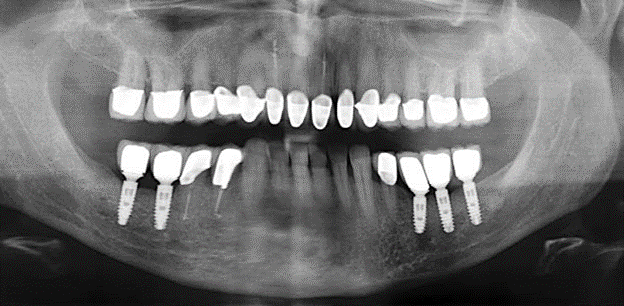

Due to the presence of periodontal disease, SPT was performed every three months in the first years following the insertion. The patient demonstrated a high degree of motivation and good compliance. The pocket depths recorded annually revealed a stable periodontal situation with a BOP index of below five per cent. On the basis of the stable periodontal situation and good cooperation on the patient’s part, the recall interval was extended to every six months as of the sixth year of the prosthetic function phase. Following the change in the recall interval, the respective annual documentation of the periodontal status continued to reveal a stable periodontal situation with no increase in the pocket depths and a BOP index below five per cent (Fig. 2a and b).

The ten-year check-up revealed no indications of advancing clinical attachment loss or peri-implant bone substance loss (Fig. 3).